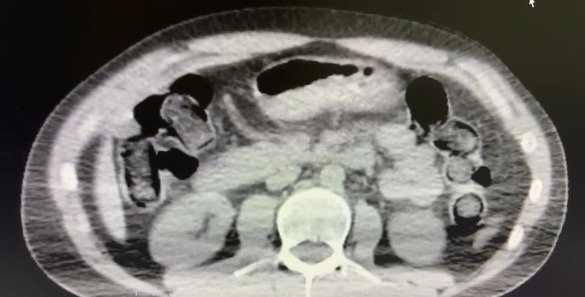

Nevşehir Cumhuriyet Başsavcılığı koordinesinde yürütülen çalışmalar kapsamında, S.B. ve O.R. isimli şahısların “yutma yöntemi” ile Nevşehir’e uyuşturucu madde sevk edeceği bilgisine ulaşıldı.

Şüphelilerin ikametlerinde ve kullandıkları araçlarda yapılan aramalarda;

- 101 kapsül halinde toplam 722 gram metamfetamin maddesi,